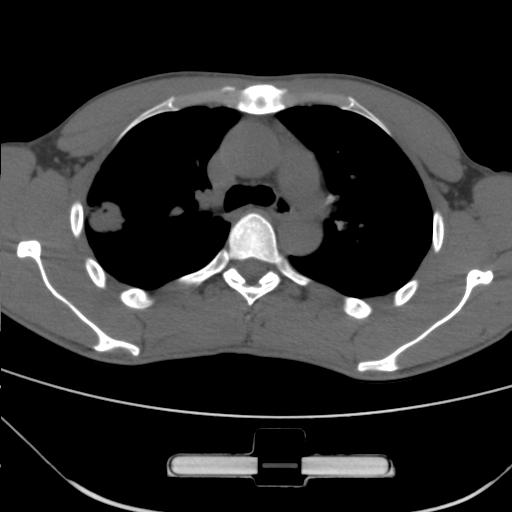

标题: CT25483:肺部病变 请指教

车祸伤者

右肺上叶后段近胸膜下结节样异常密度灶,似见分页及毛刺,考虑右肺上叶周围型肺ca,建议穿刺病理检查

周围型肺ca与炎性假瘤待鉴别。建议穿刺病理检查

缺乏病史,症状体征,但这个孤立结节具备了几乎所有的恶性征象:分叶,毛刺,空泡征,胸膜凹陷征,血管集束。